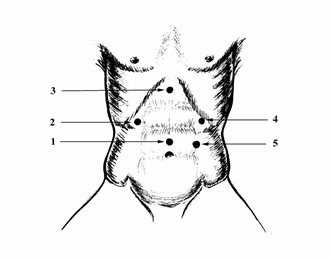

Точки установки лапароскопических портов при операции на кишечнике

Рис. 2. Оптимальные точки для введения троакаров при выполнении лапароскопической операции при ЯБДПК и ГПОД.

На рисунке показаны оптимальные точки для введения троакаров при выполнении оперативного вмешательства по поводу грыжи пищеводного отверстия диафрагмы (Рис. 2): 1 - 10 мм - для лапароскопа, 2- 10 мм - дополнительный порт для введения печеночного ретрактора, 3 - 5 мм - для введения мягкого зажима (для работы хирурга левой рукой), 4 - 10 мм - основной рабочий порт для введения ножниц, диссектора, клипсаппликатора, иглодержателя, инструмента EndoStitch, инструмента LigaSure, 5 - 10 мм - дополнительный порт для введения инструмента ЭндоБебкок и фиксации желудка и введения пищеводного ретрактора.

Отметим, что места введения троакаров могут варьировать, но всегда остается необходимость отводить печень, натягивать фундальный отдел желудка, вводить оптику и выполнять основные приемы двумя руками. Для решения этих задач необходимо пять доступов.